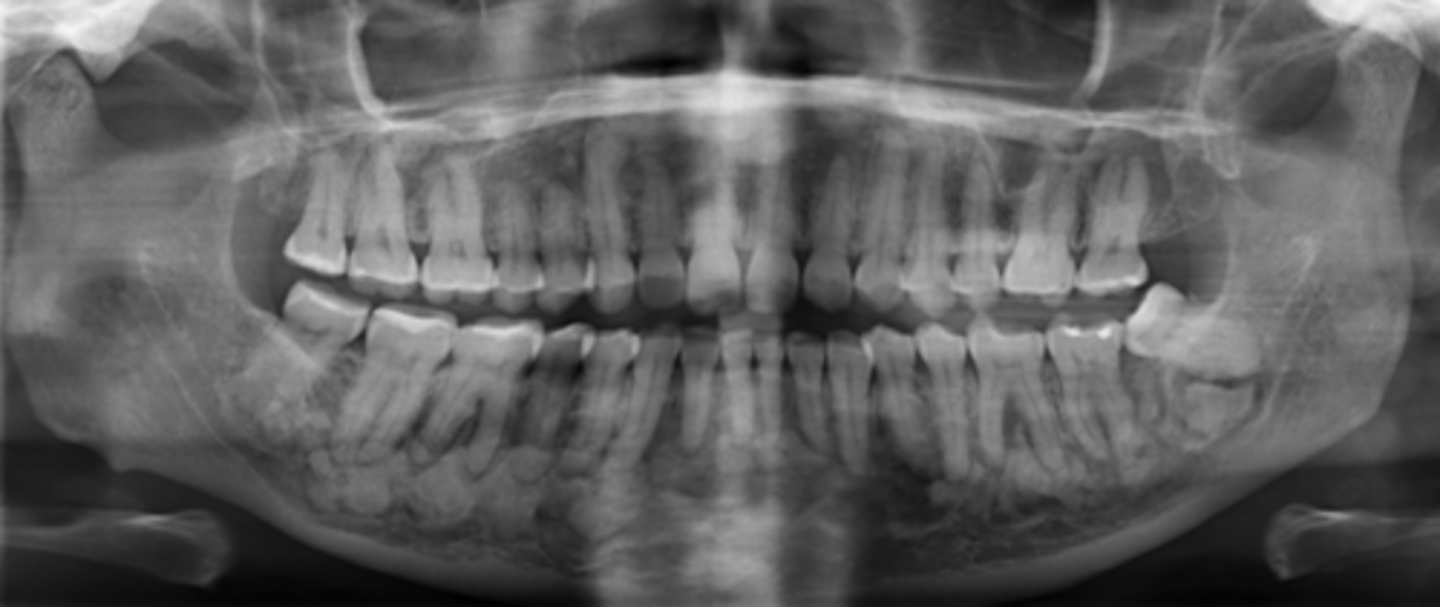

What age group is typically affected by Fibrous Dysplasia?

Young adults

What does Fibrous Dysplasia do to the IAN canal?

Displaces superiorly

What radiographic appearance does Fibrous Dysplasia have?

Ground glass opacity

What is a common clinical feature of Fibrous Dysplasia?

Unilateral facial swelling

When does growth from Fibrous Dysplasia stop?

After adolescence

Are teeth vital in Fibrous Dysplasia?

Yes

Does Fibrous Dysplasia cause pain?

No pain, no symptoms